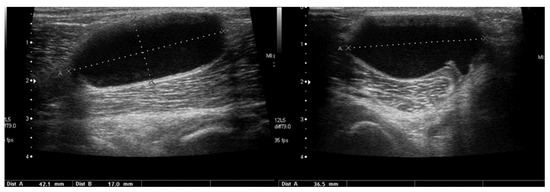

3.2.2. Osgood–Schlatter Disease

3.2.3. Ligament Injuries